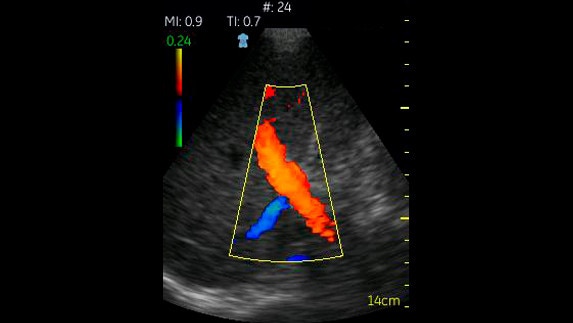

Vasküler